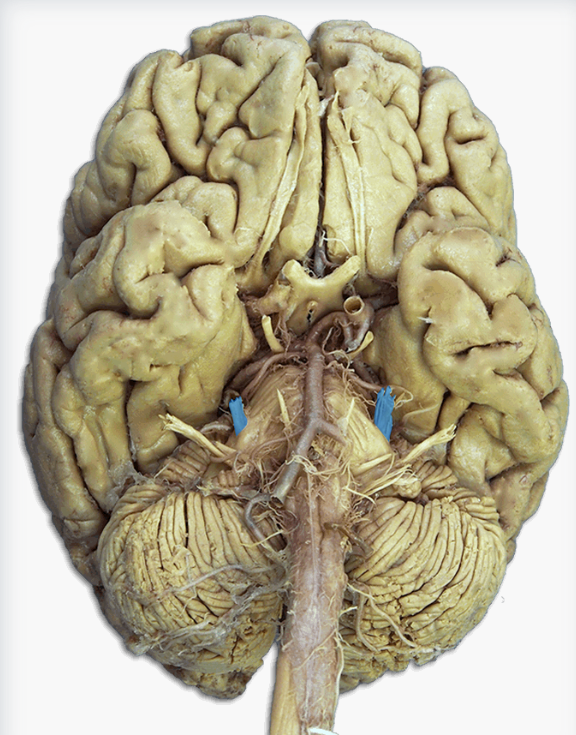

Label this cranial nerve

Olfactory (CN I) nerve

Label this cranial nerve

Optic (CN II) nerve

Label this cranial nerve

Oculomotor (CN III) nerve

Label this cranial nerve

Trochlear (CN IV) nerve

Label this cranial nerve

Trigeminal (CN V) nerve

Label this cranial nerve

Abducens (CN VI) nerve

Label this cranial nerve

Facial (CN VII) nerve

Label this cranial nerve

Vestibulocochlear (VIII) nerve

Label this cranial nerve

Glossopharyngeal (CN IX) nerve

Label this cranial nerve

Vagus (CN X) nerve

Label this cranial nerve

Accessory (CN XI) nerve

Label this cranial nerve

Hypoglossal (CN XII) nerve